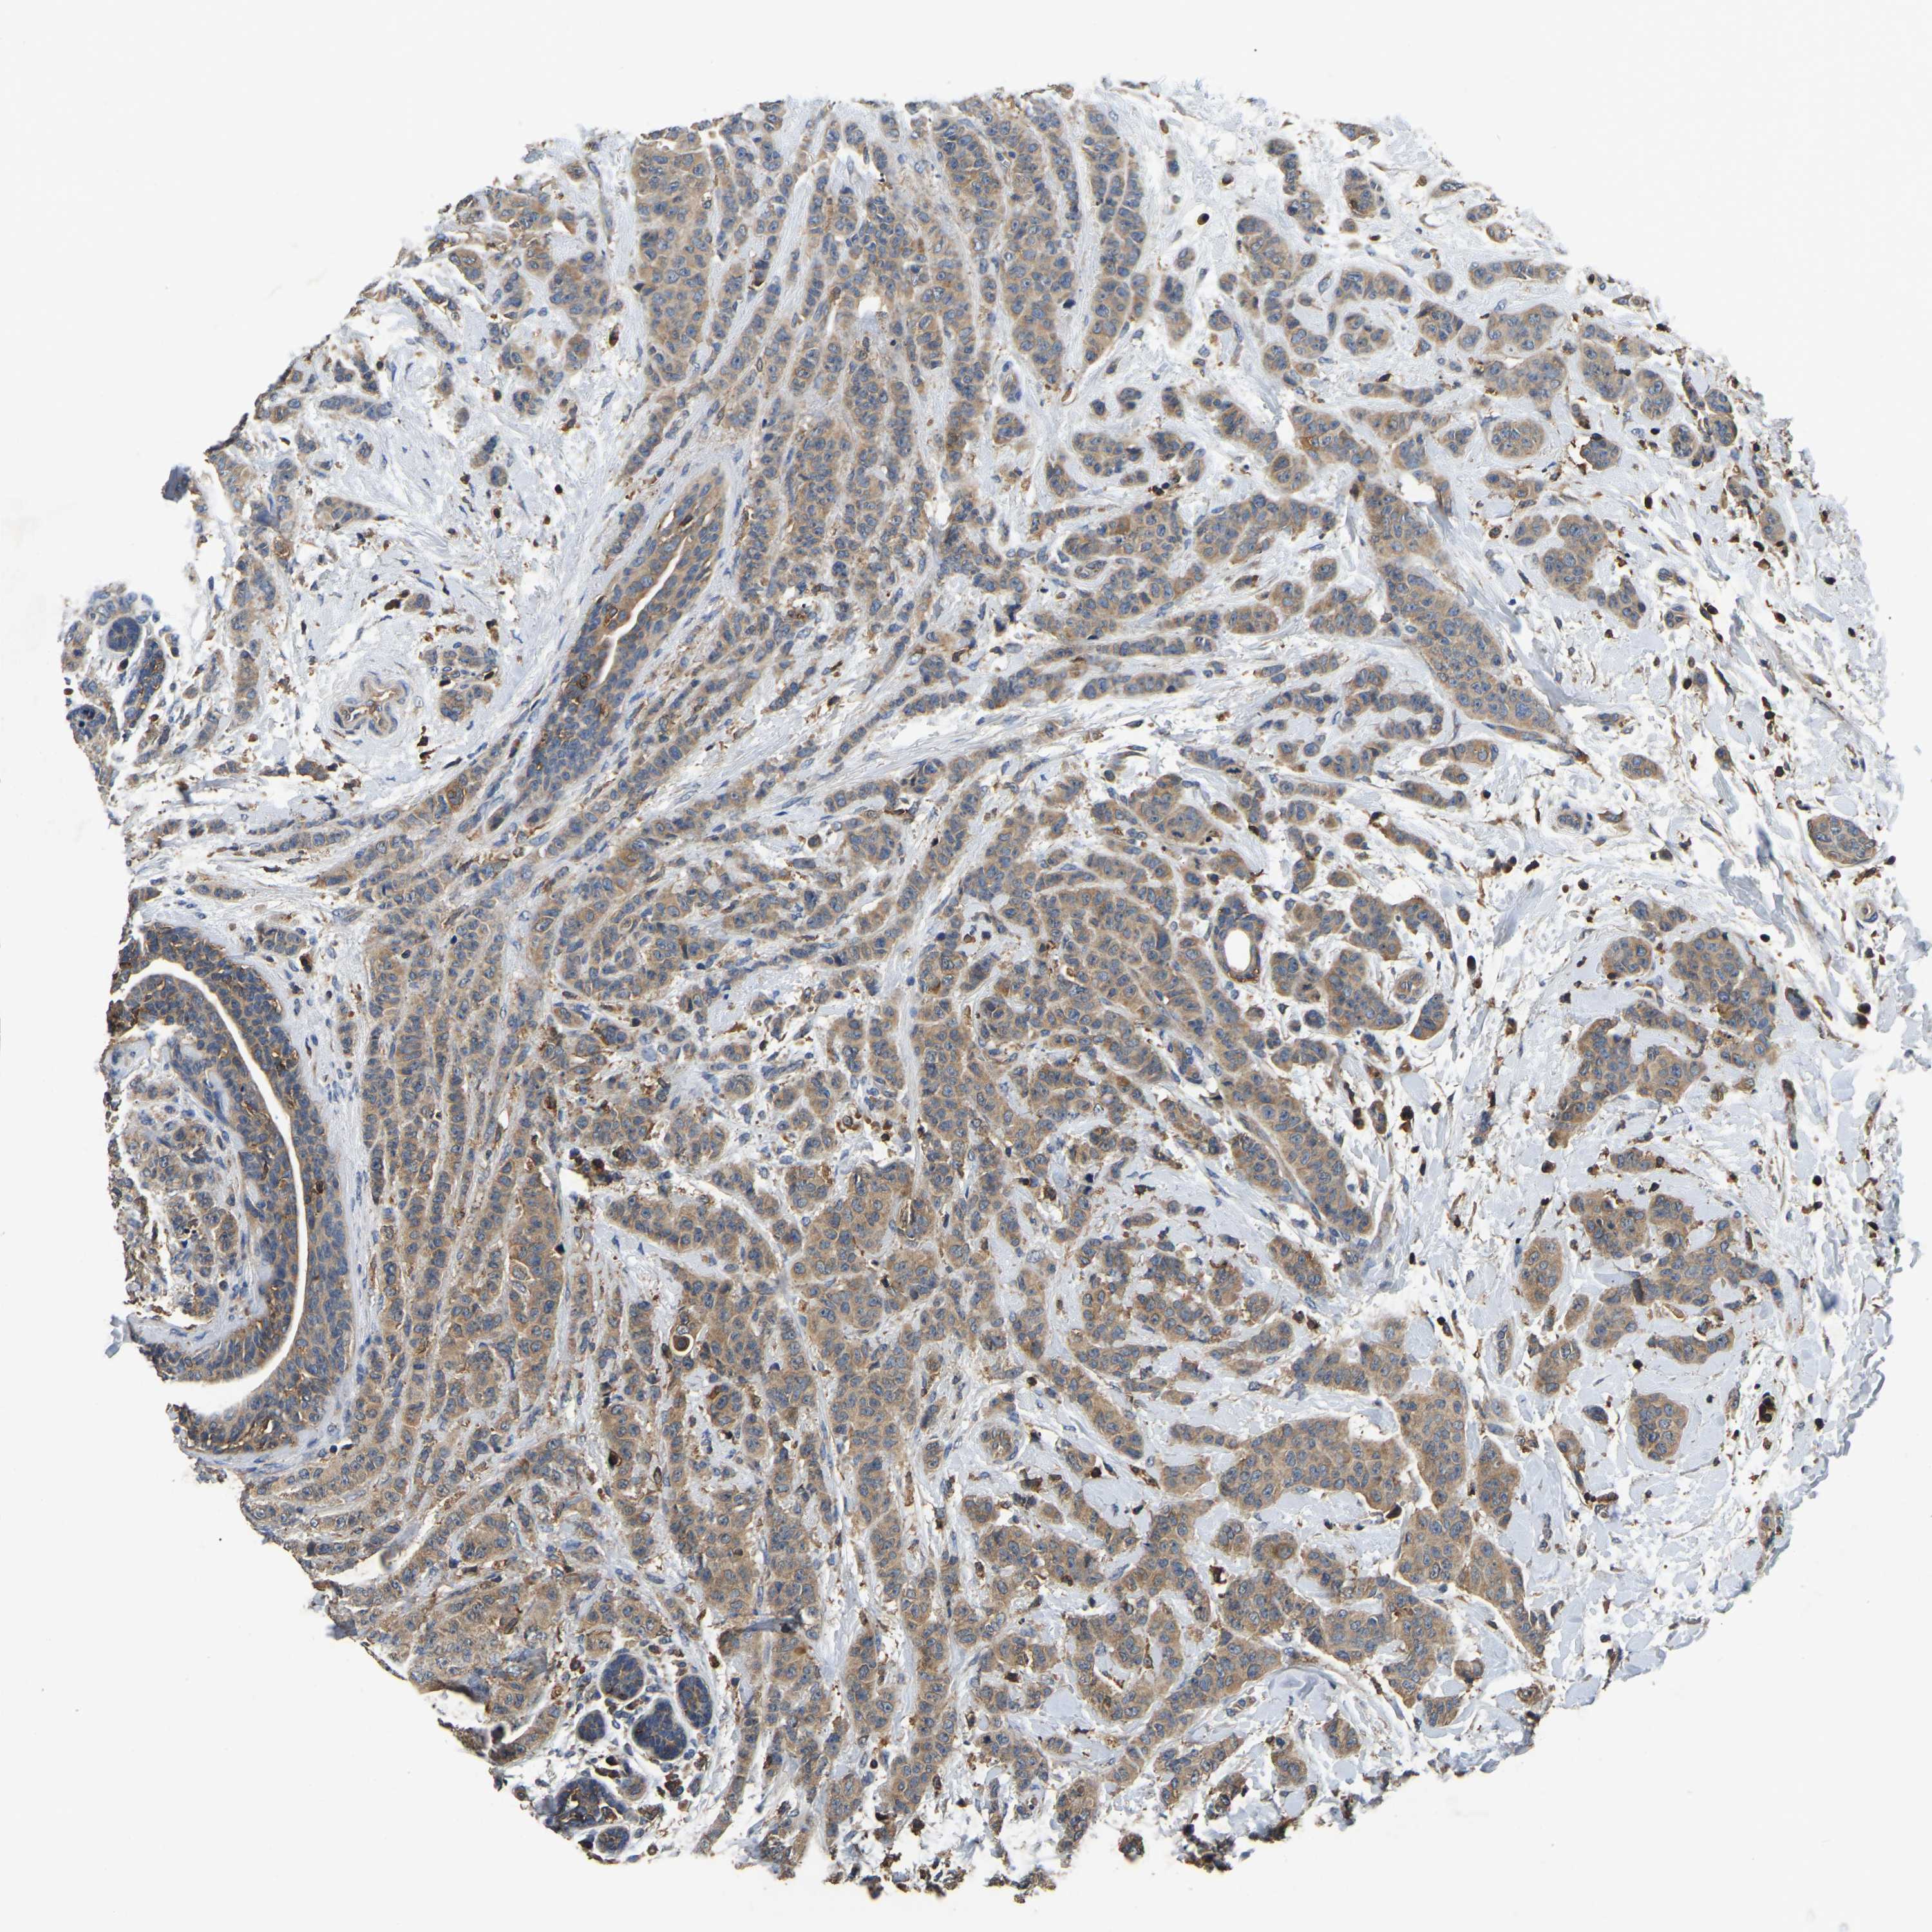

CANCER BREAST CANCER Show tissue menu

BRCA TCGA BRCA VALIDATION PROTEIN EXPRESSION